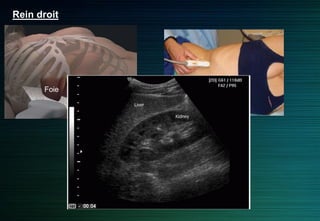

Rein droit

Abord latéral ou antérolatéral

Foie: fenêtre acoustique

(antérolatéral)

Incidence intercostale: pôle supérieur

Foie

Rein